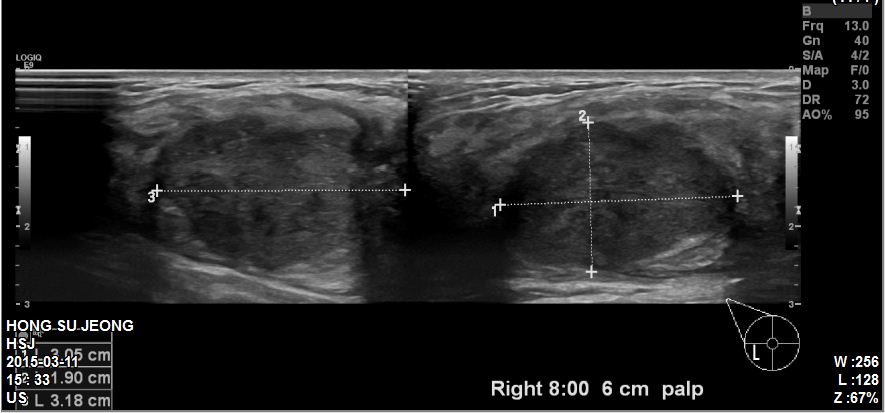

본원에 내원하신 40대 환자분이십니다.

유방초음파 및 우측유방에 혹 조직검사와

우측겨드랑이에 림프절 세침검사 시행하였고

침윤성유관암 진단되었습니다.